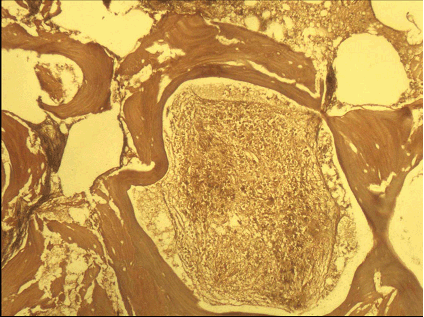

A 14-years-old female child, already a documented case of Down's syndrome proved on cytogenetic analysis, presented to our institute with fever of five days duration associated with bleeding from nose and mouth. Clinical examination of the patient revealed features of Down's syndrome like short stature, macroglossia, low set ears, simian crease and delayed milestones. Abdominal examination revealed palpable splenomegaly two cm below the costal margin. There was no hepatomegaly. Her hematological parameters showed hemoglobin of 3.2 g/dl, total leukocyte count of 3x103/mm3 with normal differential count and platelet count of 2x105/mm3. Examination of blood film did not reveal any immature cells. Erythrocyte sedimentation rate was 84 mm/1st hr. The biochemical parameters were within normal range. She was subjected to bone marrow examination. Bone marrow aspiration revealed a dry tap. Bone marrow biopsy revealed a hypocellular marrow showing presence of granulomatous inflammation consisting of epithelioid cells, Langhan's giant cells, lymphocytes and plasma cells with central areas of caseation necrosis (Figure 1, 2). Ziehl-Neelsen (ZN) staining for AFB was positive. Areas of marked fibrosis with pockets of increased number of megakaryocytes and fibroblasts were present. Reticulin stain showed increased bone marrow reticulin fibres (Figure 3), thus supporting the diagnosis of myelofibrosis. There was no evidence of any leukemic involvement. Since the patient hailed from tuberculous endemic area, diagnosis of myelofibrosis secondary to tuberculosis was contemplated. The patient was put on a course of antitubercular treatment (ATT). Unfortunately she was lost to follow up; therefore repeat bone marrow biopsy could not be done to assess the course of the disease.

Figure 2: Higher magnification showing granulomatous infiltrate replacing the hematopoietic cells. (H&E, x200).